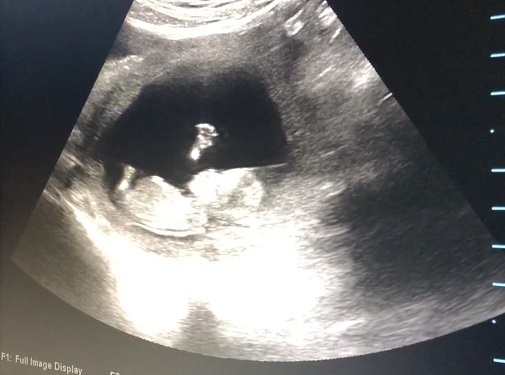

11週1日(11w1d・男の子)|naaaatsu3u さん(28歳)

エコー写真撮影時のエピソード:

前回妊娠した時はエコー写真で赤ちゃんの形がよくわからない段階で流産してしまいました。

なので、このエコー写真で赤ちゃんが2頭身になり、手足がはっきり見えた時はとってもうれしかったです。